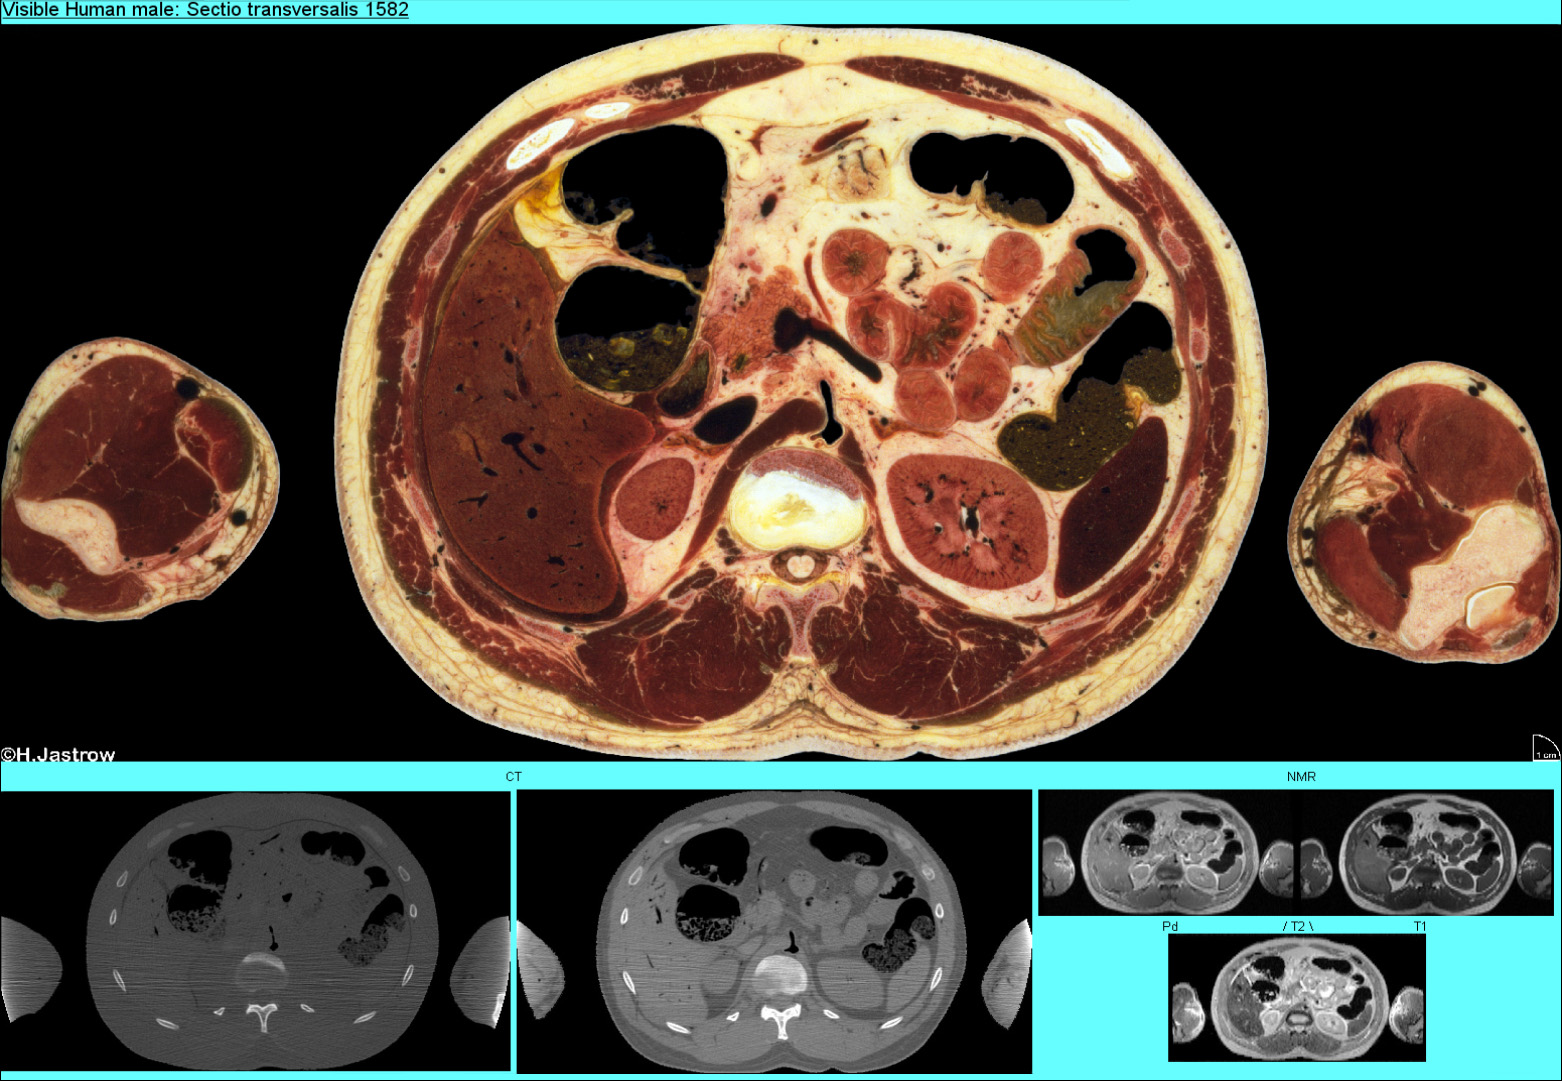

Abb.28 zeigt eine Seite mit einem Schnitt durch den Bauchraum mit Leber, Nieren, Milz und der Bauchspeicheldrüse.

Abb.28

Beachten Sie, daß an dem in Abb.29 gezeigten, beschrifteten Schnitt 120 Bezeichnungen angebracht sind. Damit die Übersicht dennoch erhalten bleibt, kreuzen keine Linien.